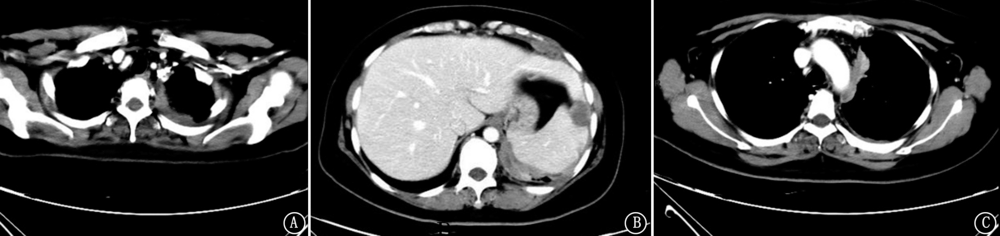

宫颈癌的主要转移途径是直接蔓延、淋巴转移和血行转移,较常见的远处转移部位为肺、肝、骨骼等,宫颈癌胸膜转移报道较少,现报道1例宫颈癌发生胸膜转移并快速进展导致死亡的病例,以提高对少见部位转移的宫颈癌的重视。